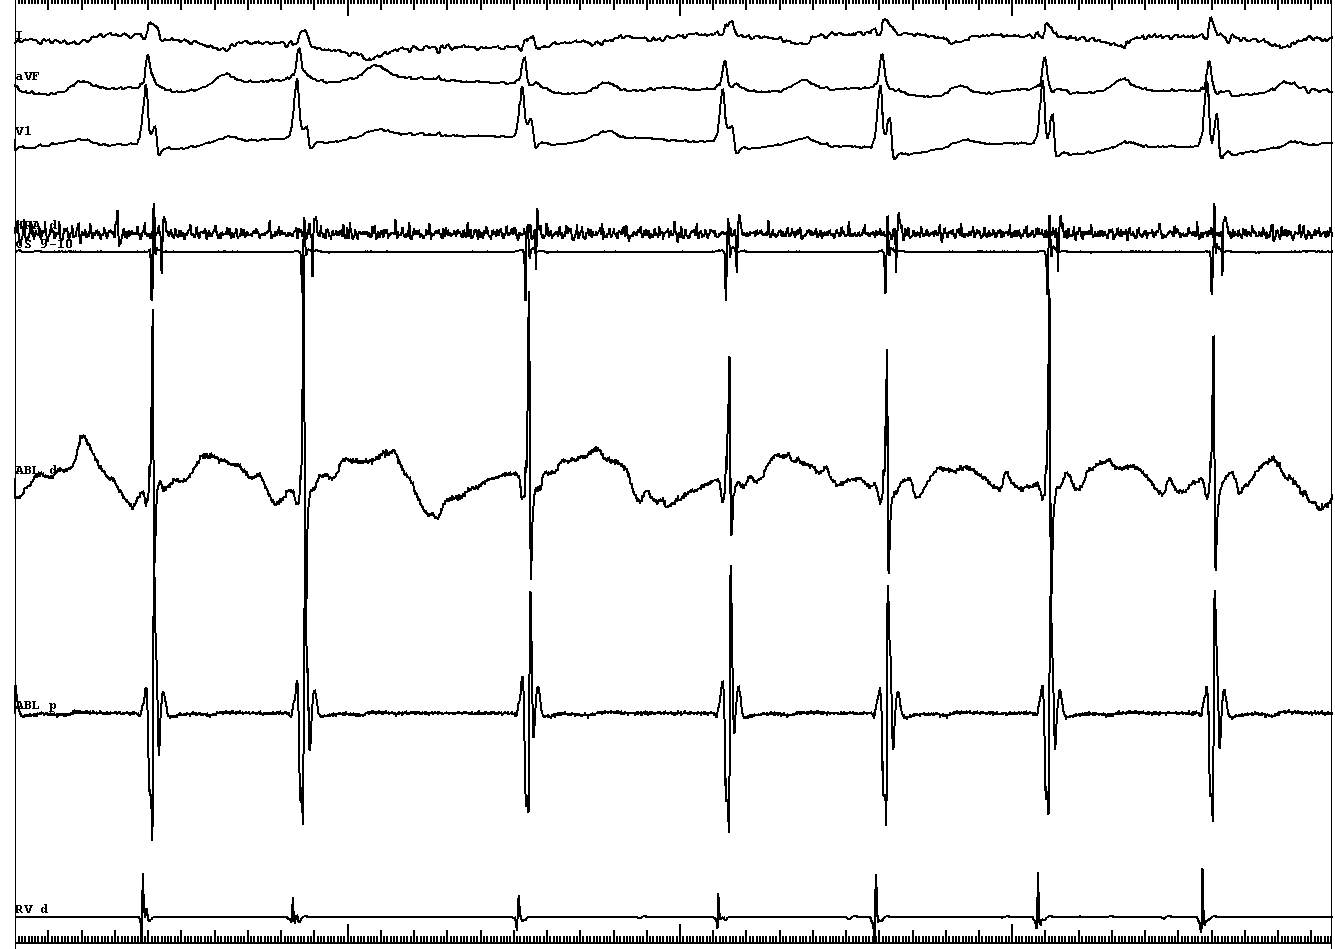

• VA conduction with His after A - ? AP

tachy_2.jpg

• VA conduction with His after A - bystander His activation, ? AP

• VH block with VA conduction - further confirms bystander His

tachy_3.jpg

• Short VA during tachycardia - not AVRT

• Narrow QRS similar to sinus - antegrade conduction through another AV node

tachy_4.jpg

• Internodal tachycardia ? - A before His, tachy continues with VH block

• Therefore, AVNRT involving inputs to anterior node